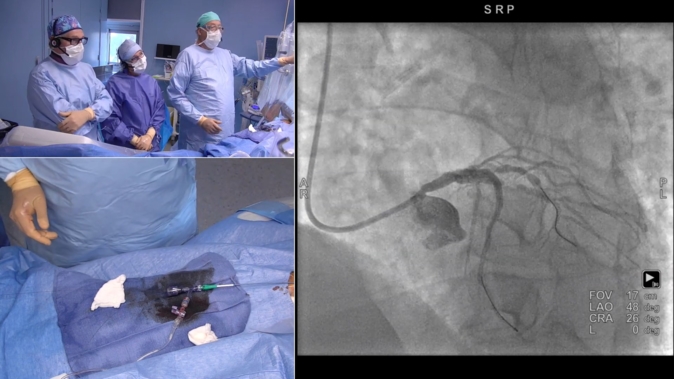

How should I prevent and manage complications when performing left main PCI?

08 Mar 2022

Watch the replay of this PCR Webinar on bifurcation with G. Stankovic, J. Fajadet, T. Lefèvre and J. Legutko.